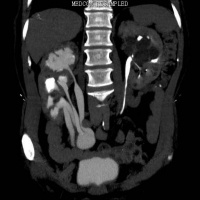

静脉泌尿造影可清楚显示功能良好的重复肾及双输尿管畸形,对功能不良的重复肾则容易误诊

CT检查可清晰显示重复肾畸形及合并积水的双输尿管, 能更清楚的显示重复肾的内容,同时CT连续层面观察可确定输尿管的异位开口,但对无扩张的重复输尿管显示不够清晰,直观。